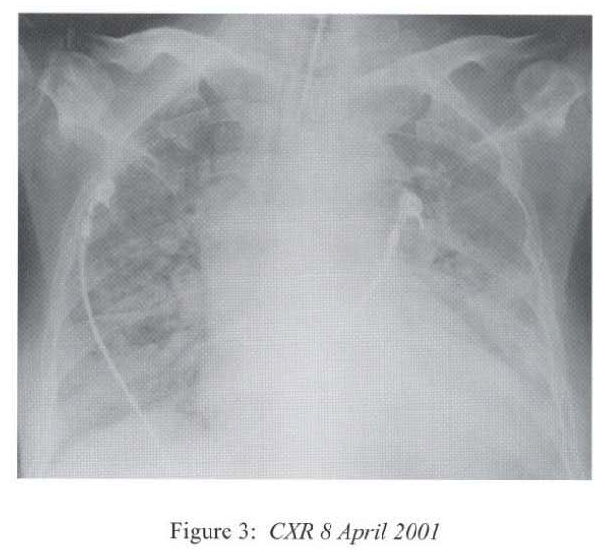

She was admitted to the medical ward on 17th March 2001 complaining of exertional dyspnoea, fever, chills and rigor. CXR showed right lower zone patch of consolidation (Figure 1) while baseline CXR in January 2001 was normal. She was treated with 1 week’s course of Ceftazidime. Steroid was continued while the cyclophosphamide was stopped. Fever resolved and the chest symptoms improved. However there was further deterioration of renal function in the next 10 days(creatinine 333–;>693 umol/L; creatinine clearance 8ml/minute). The clinical impression was progression to cresentic glomerulonephritis and she soon developed anuria before renal biopsy could be repeated and required peritoneal dialysis.

Radiological features are also diverse and variable 15,16.On the chest radiograph, early signs include miliary shadows, diffuse reticular interstitial opacities, patchy alveolar opacities, segmental or lobar opacities. In the advanced stage, there can be extensive airspace shadows affecting both lungs, with occasional pleural or pericardial effusion. Without treatment, ARDS quickly evolves. Rarely, ARDS develops after antihelminthic treatment due to release of toxic breakdown products 17.On the abdominal radiograph, there can be thickened mucosal folds, segmental small bowel dilatation or perforation. Among all these variable radiological features, a characteristic pattern of Strongyloides hyperinfection has been described by the radiologists of Hong Kong, which consist of fleeting and rapidly changing CXR signs, predominant small bowel abnormality on AXR, and close temporal relationship of CXR & AXR signsl8. Detection of larvae in stool or other specimens is difficult (Table 1). Serological diagnosis19 is an attractive alternative but it is not available in Hong Kong.